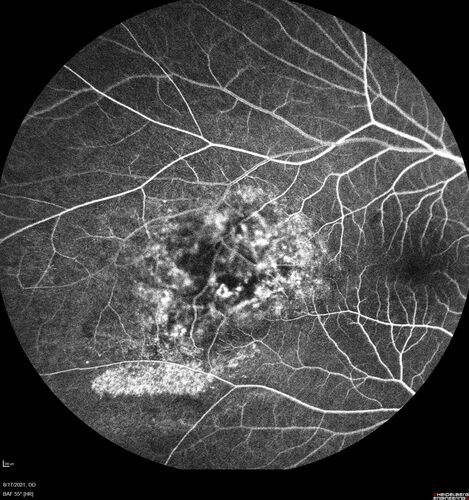

Choroidal Hemangioma Requiring PDT repeatedly

64 year old man.  Diagnosed with hemangioma in 2015.  PDT in 2016.  Images are from 2020 when fluid started to reaccumulate.  Needed PDT repeated two more times.

PDT treatments: [1] 2/19/2015 -  Pavan (IOP  problem after PDT)  AND [2] 11/2/21 PDT (7 mm temporal to fovea) - SMC  AND [3] 7/22/22 PDT 7.5 mm Temporal to the fovea